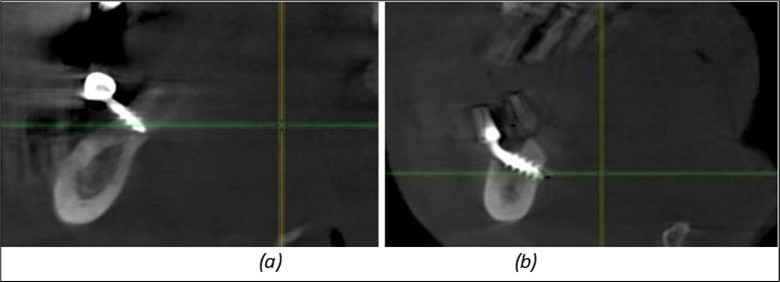

Figure 13.Corticobasal BCS implants fixed between the vestibular and lingual cortices with support on the basal bone: (a) BCS fixed between the lateral cortices; (b) BCS implant with support on the basal cortex.

Figure 14.Rx panoramic final situation control: (a) Panoramic X-ray with the addition of a distal BCS implant in quadrant 3 at 11.2022; (b) Control X-ray, 10.2023.

The results of rehabilitation treatment with corticobasal and compressive implants with a polished surface after the failure of two stage implants were highlighted over a period of 3 years and 3 months as being very good (Figure 14, Figure 15), with the patient completing a satisfaction survey in this regard. Certainly, it is necessary to continuemonitoring these results in the long term.